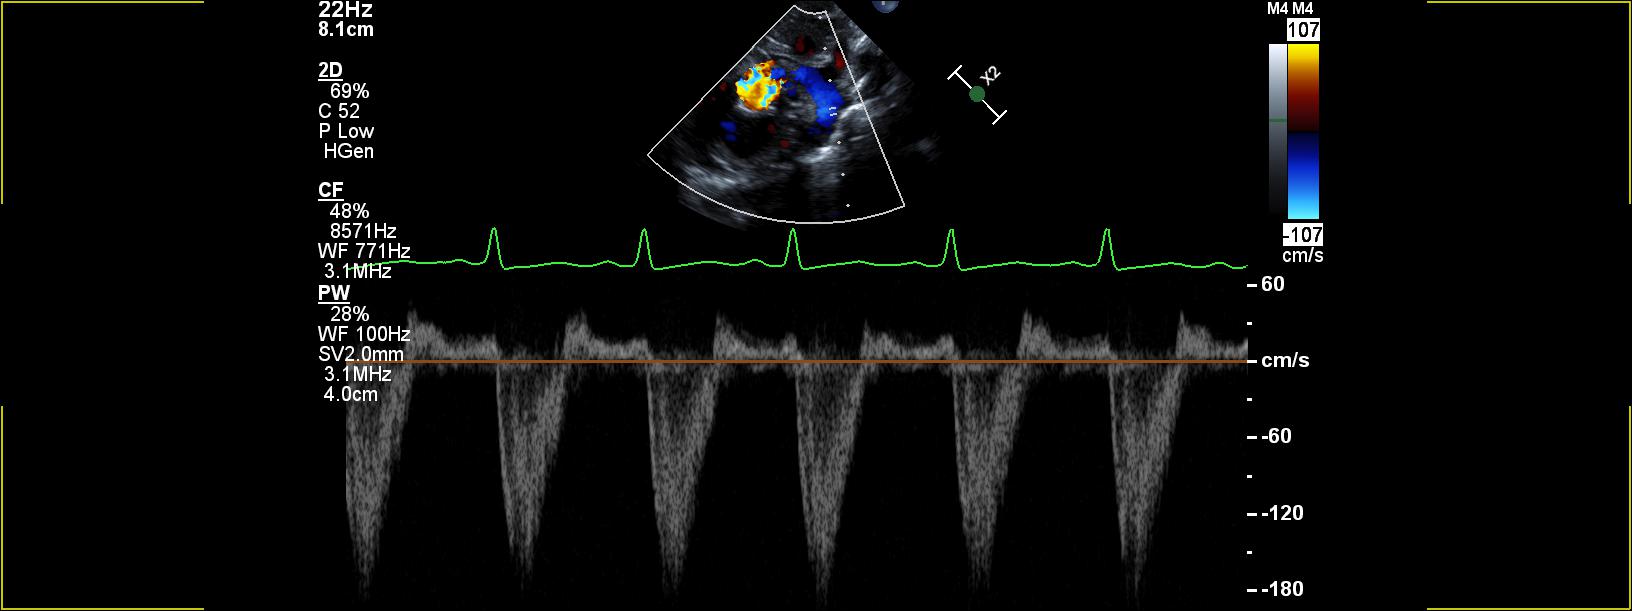

A transthoracic echocardiogram (TTE) has findings of a malaligned atrial septum and a small left-to-right atrial (RA)–level shunt (Video 1). There is no ventricular septal defect or patent ductus arteriosus (PDA). The right ventricular (RV) size, function, and pressure estimates are normal. The left heart appears dilated with normal left ventricular (LV) systolic function. A large vessel appears to drain to the left atrium (LA) (Video 2). An agitated saline contrast injection (bubble study) is performed using a peripheral intravenous line in the right upper extremity (Video 3).

LA drainage of a right superior vena cava (RSVC) is an exceedingly rare congenital heart defect. When present as an isolated defect, this defect typically results in mild cyanosis due to desaturated systemic venous blood from the upper body mixing with fully saturated pulmonary venous blood in the LA.1 Drainage of upper-extremity venous blood returning to the LA in this patient was confirmed by agitated saline contract injection into a right upper-extremity vein, which demonstrated immediate opacification of the LA and LV (with some crossing over into the right heart via the small atrial shunt). Findings on computed tomography angiogram (CTA) confirmed the etiology of this abnormal drainage to be an RSVC draining exclusively to the LA with no connection to the RA (Image 1). The right middle and right upper pulmonary vein were demonstrated to drain into the rightward and posterior aspect of the RSVC (partial anomalous pulmonary venous return). The right lower and all left-sided pulmonary veins drained normally to the LA. A small secundum atrial septal defect was noted to be remote from the cavoatrial connection with an atrial septum that was malpositioned rightward. The branch pulmonary arteries appeared mildly hypoplastic. She was discharged home on room air with goal SpO2 levels of ≥85%.